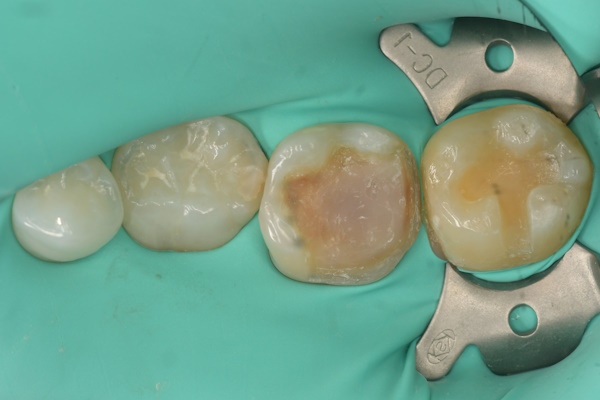

セラミック治療の治療例です。奥歯の詰め物に違和感があり、食べ物が詰まりやすいとのことで来院されました。当院にて診査を行ったところ、隣接する歯の咬合面にも虫歯が認められたため、2本同時に虫歯治療を行い、セラミックによる修復を実施しました。セラミックは隣接面の形態再現性やコンタクトの精度に優れているため、治療後は食べ物の詰まりが改善され、違和感も解消されました。オキシガードは、過酸化物と還元剤による化学重合反応により、歯科接着用レジンセメント表面の未重合層を硬化させる材料です。さらに、未重合層を空気から遮断することで確実な硬化を促します。また、接着効率をあげるためにラバーダムを使用して治療を行っております。

虫歯処置後